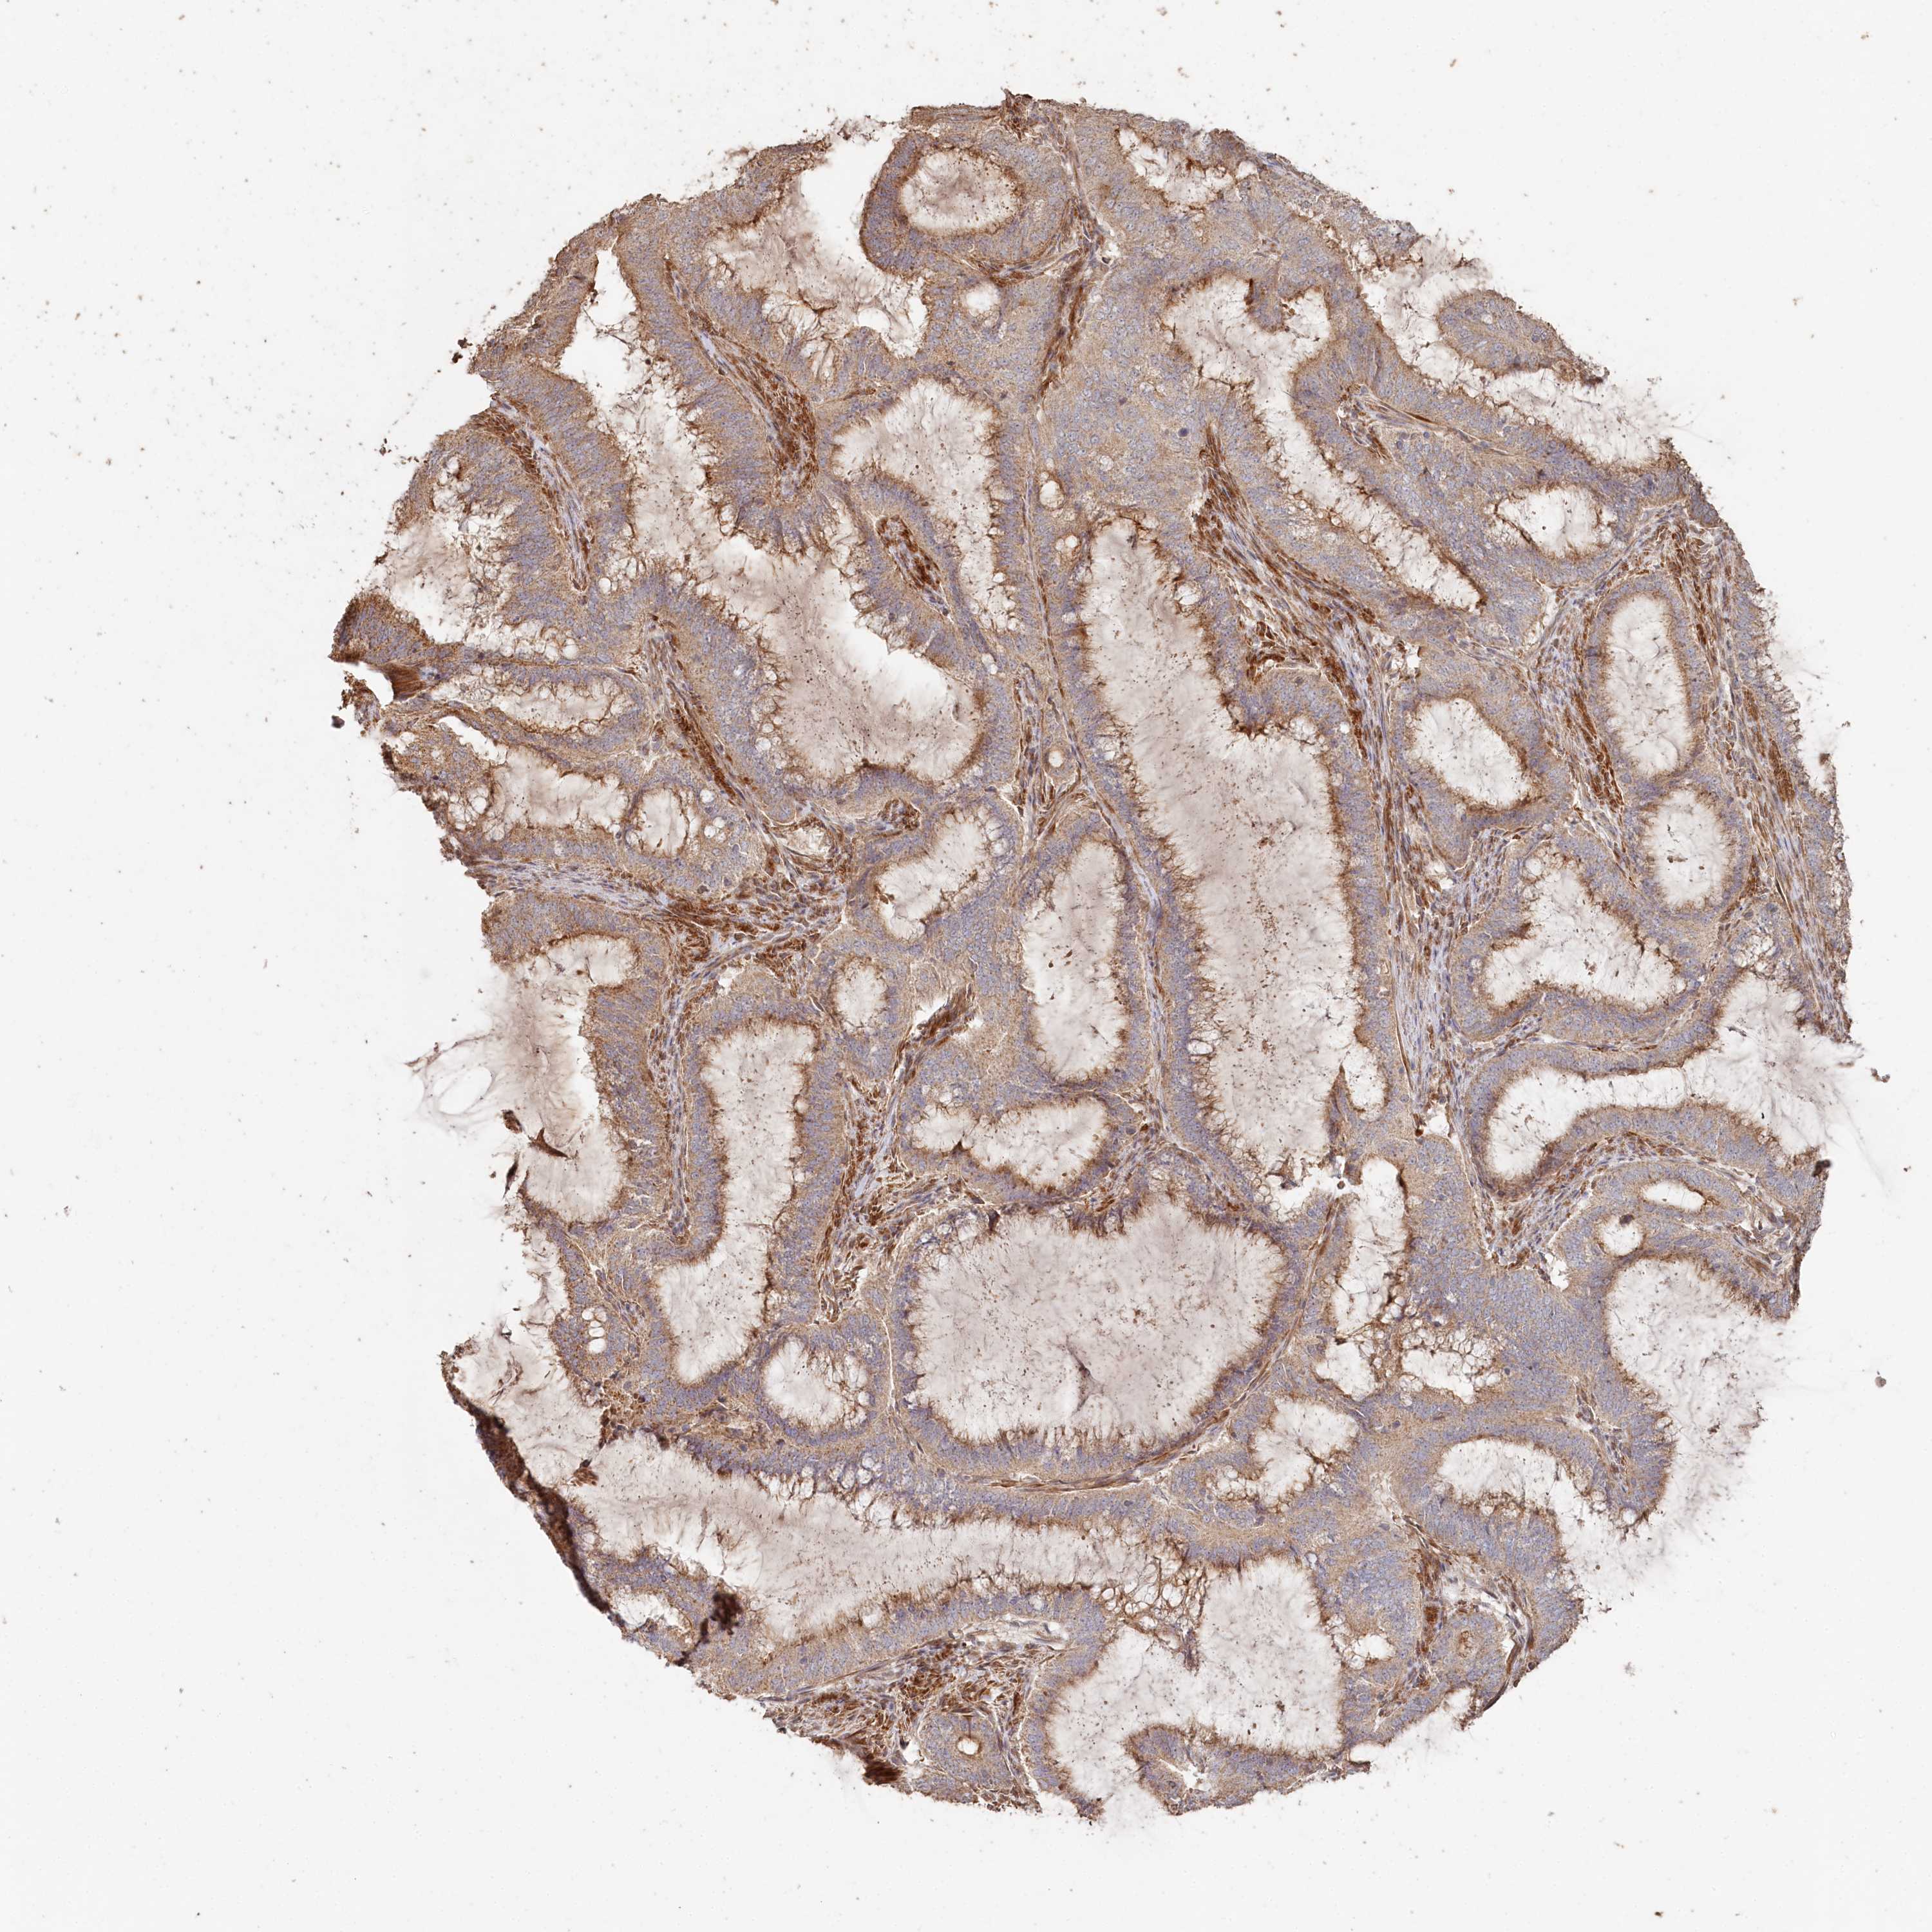

ENDOMETRIAL CANCER - Protein expressioni

A mouse-over function shows sample information and annotation data. Click on an image to view it in a full screen mode. Samples can be filtered based on level of antibody staining by selecting one or several of the following categories: high, medium, low and not detected. The assay and annotation is described here.

Note that samples used for immunohistochemistry by the Human Protein Atlas do not correspond to samples in the TCGA dataset.

Antibody stainingi

Antibody staining in the annotated cell types in the current human tissue is reported as not detected, low, medium, or high, based on conventional immunohistochemistry profiling in selected tissues. This score is based on the combination of the staining intensity and fraction of stained cells.

Each image is clickable and will lead to virtual microscopy that enables deeper exploration of all samples and also displays staining intensity scores, fraction scores and subcellular localization as well as patient and tissue information for each sample.

Antibody HPA038547

Antibody HPA038548

Staining

High

Medium

Low

Not detected

Intensity

Strong

Moderate

Weak

Negative

Quantity

>75%

75%-25%

<25%

None

Location

Nuclear

Cytoplasmic/membranous

Cytoplasmic/membranous,nuclear

Adenocarcinoma, metastatic, NOS